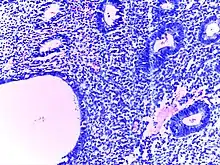

![]() | Follicular lymphoma | Micrograph showing a small B-cell lymphoma compatible with follicular lymphoma. H&E stain. | Category: Histopathology of follicular lymphoma | Follicular lymphoma |